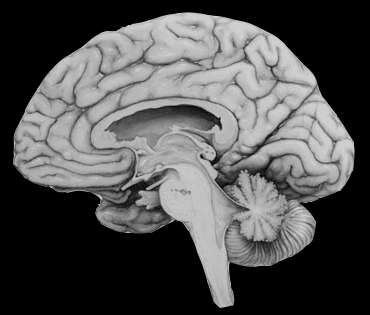

Je ne retrouve pas la source de cette image

Si c'est la votre et contactez-moi, je mettrai le lien vers la source

Je l'enleverai rapidement si il le faut